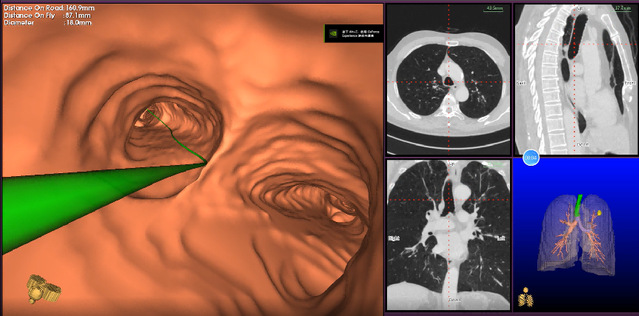

作为介入呼吸病学的**进展,电磁导航支气管镜技术是现代电磁导航技术、虚拟支气管镜和三维CT成像技术相结合的新一代支气管镜检查系统。该系统如同肺部的GPS导航系统,能够建立一条直达肺内病灶的精准诊疗通道,对肺部病变尤其是肺小结节病灶的诊断更准确,与传统诊断方法比较有显著的优势。苏州九院呼吸与危重症医学科副主任董凌云提前将李先生的高分辨率CT图像导入磁导航系统,构建确定了“GPS导航”路径。在麻醉医生的配合下,呼吸与危重症医学科副主任张剑锋利用电磁导航支气管镜诊疗技术,在纵横交错的“支气管交通网”中,按照系统提前规划的“GPS导航”路径,可视化操作支气管镜,精准到达左肺上叶后段结节处“目的地”,成功获取了左肺上叶后段结节的病理活检组织,并给予肺泡灌洗送NGS检测,顺利完成吴江区域内首例“电磁导航支气管镜检查”,开启了吴江地区肺部外周病灶精准诊疗模式。

近年来,随着计算机断层扫描肺部筛查的普及,筛查期间发现了很多的外周型肺结节,这些外周型肺结节的性质单从影像学上无法分辨,明确诊断需依靠病理检查。但经气管镜穿刺或活检很多时候无法到达外周型肺结节的位置,可能需要进行并发咯血、气胸、血胸等风险较高的CT引导下经皮肺穿刺才能取到病理,且该项检查患者辐射暴露的风险亦增加。而磁导航支气管镜检查则突破了传统支气管镜检查的应用瓶颈,该项检查是一种将磁导航系统、支气管镜检查以及CT三维重建技术相结合的新技术:在患者CT影像的基础上,通过建立肺部“GPS导航”地图,利用体外磁场定位板来进行实时引导定位电磁导航支气管镜操作,使得定位导线和鞘管快速精准地到达肺部的每一个角落,可以精准定位肺外周靶病灶、开展活检及治疗。